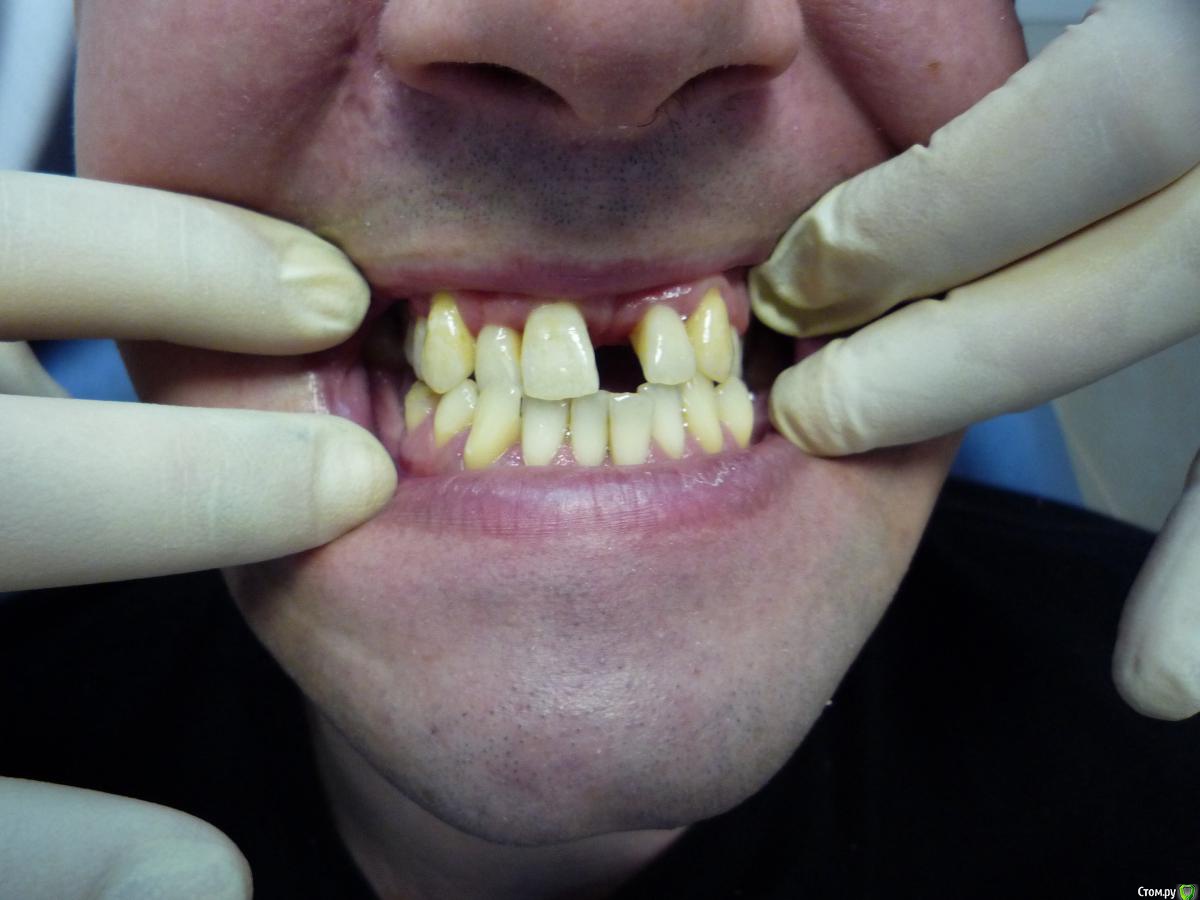

Jeniaspb Опубликовано 20 июля, 2015 Поделиться Опубликовано 20 июля, 2015 Пациент 32 года. Фото к сожалению только те, что есть. По ТРГ верхняя микрогн и нижняя прогнатия, протруз резцов в/ч 132^ и ретрузия резцов н/ч 68^, а так же переднее положение головки н/ч. Идеально сделать гнатич хирургию, но пациент идет в полный отказ, в связи с чем имеются следующие мысли:1) провести ТЭНС терапию с определением положения н/ч, в надежде на то, что она сместится хоть чуточку назад.2) если н/ч сместится каппа на н/ч с последующ окклюз накладками3) б/с на нижн зубн ряд и попыткой смещения дистально премоляров для освобожд места резцам4) б/с на в/ч и попытки камуфляжа этого всего...5) имплантация и затем протезирование.Вопрос самый главный:на сколько велики мои шансы сделать обратное перекрытие, которое я не смогу вернуть?) Ссылка на комментарий

Yana guapa Опубликовано 22 июля, 2015 Поделиться Опубликовано 22 июля, 2015 Есть подозрения на нарушения внчс, н/ч имеет норм размеры, опять таки есть подозрения, что н/ч занимает не центральное положение! только подозрение?)) при таком положении НЧ , при таких дефектах зубных рядов дисфункция обязана быть)) Каким образом: расслабление мышц приведет н/ч в ее центр положение. Что: изменение положения н/ч за счет см вышеДля чего: перемещ н/ч назад в идеале! какой смысл проводить сейчас "расслабление" если НЧ физически не сможет сместиться назад при обратном перекрытии 1.2 зуба (это же блок). или Вы хотите сделать немалое разобщение , увеличив ротацию НЧ, и о каком расслаблении тогда речь? мне не понятно. (имхо) Ссылка на комментарий